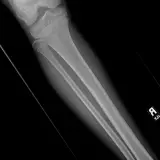

Over 2,100 interactive radiology cases, curated by radiologists for your level of training. Scroll, window, and view cases full screen — just like on PACS. Click linked findings in each writeup to jump straight to them on the image. Cases include sample reports, a focused discussion section, original illustrations, and videos.

Casos totalmente interactivos con las herramientas que esperaría de un PACS: scroll, ventana, zoom, pan, mediciones, ROI y modo de pantalla completa.

• Anotaciones enlazadas

Anotaciones extensas resaltan los hallazgos clave directamente sobre los casos. Haga clic en los hallazgos enlazados dentro de la descripción del caso para saltar a su ubicación exacta en el estudio.

Aprenda con eficiencia gracias a hallazgos de imagen anotados e ilustraciones